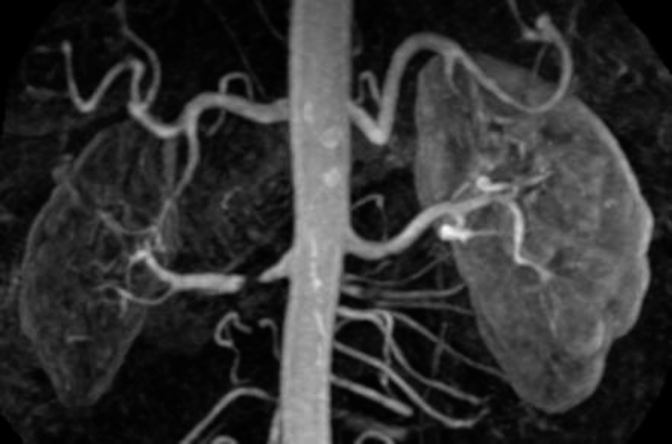

- MRA/CT: (magnetic resonance angiogram)

- More clear images * done if u/s doppler not clear * MRA is also non-invasive like Doppler

Angiogram showing renal art. stenosis

ANGIOGRAM

“String of beads” appearance of renal artery in fibromuscular dysplasia